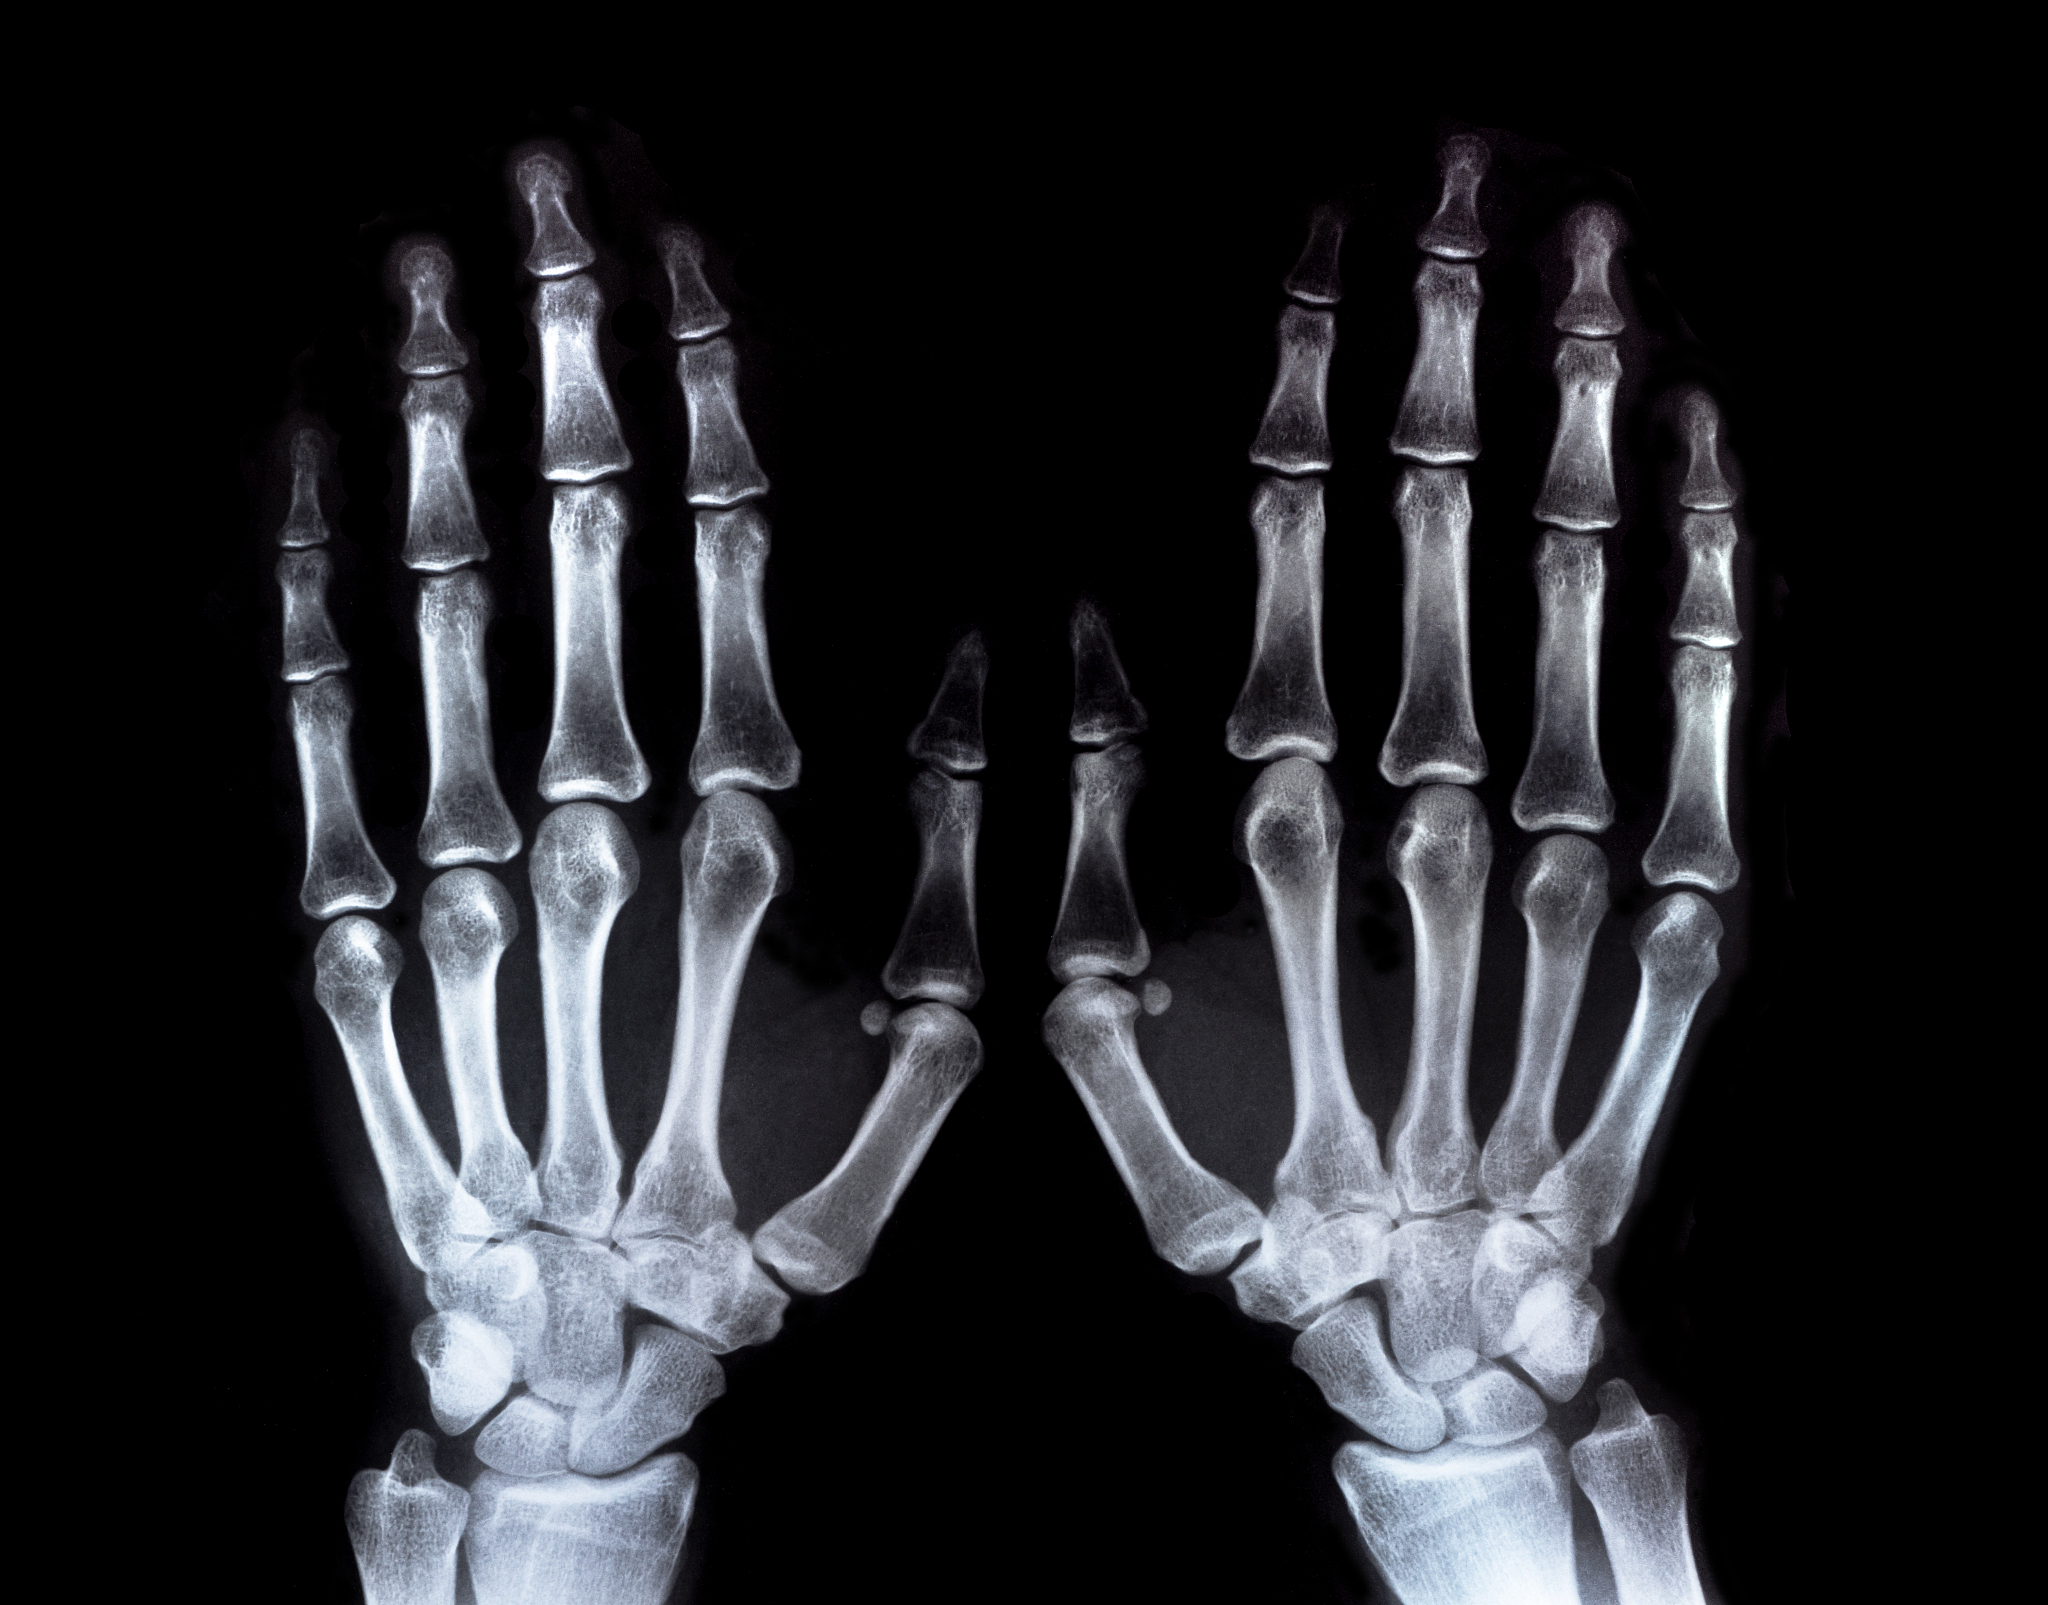

手指长度是指从指尖到手掌的长度,正常手指长度为6-8厘米。如果手指长度小于6厘米或大于8厘米,就属于手指畸形。指间距是指相邻两个手指之间的距离,正常指间距应该相等,如果指间距不相等,就属于手指畸形。指弯曲度是指手指的弯曲程度,正常手指弯曲度应该能够自由弯曲,如果手指弯曲度过大或过小,就属于手指畸形。

除了以上几个方面,还有其他一些手指畸形的表现,如手指过于细长或短粗、手指关节僵硬等。这些手指畸形都会影响士兵在军事训练和作战中的表现和效率。